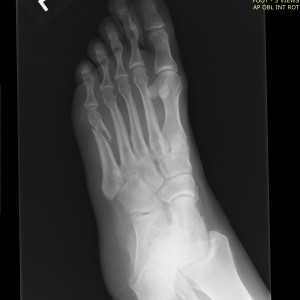

This challenge came at just the right time. I recently severely sprained my ankle and broke a bone in my foot. I am a runner and work a physically demanding job, this was a devastating setback. I was couch bound and fell into a bit of a depression after learning that it will take around six months for me to fully heal and there will be absolutely no running for a while after that. I am an active person and live in a very active community. Living vicariously through other people's postings on Facebook is not conducive to a mentally healthy life for me. I told myself, this mornng, to quit feeling sorry for myself and get my butt "back in the saddle" on the stationary bike. It was exhilarating to feel the sweat drip and feel my heart pound back to life. Then I saw this post from Jen and knew that was just the thrill of the chase that I needed. I want to prove to myself that I have what it takes, injury aside, to still beat the demon of complacency!